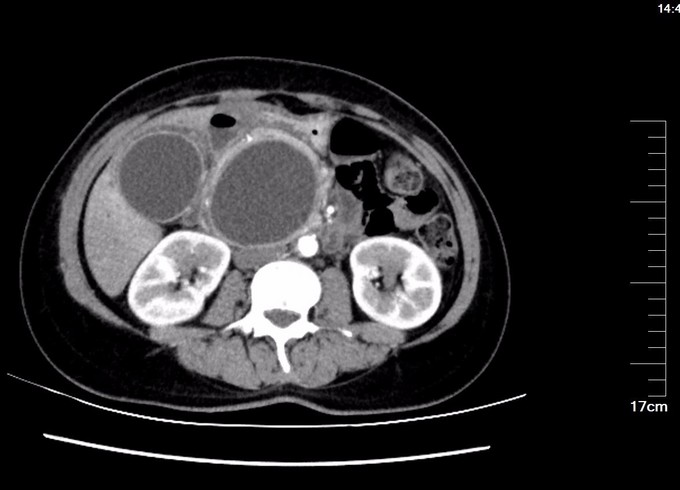

查体:腹部略膨隆,未见胃肠型及蠕动波,未见腹壁曲张静脉,右上腹部压痛阳性,无反跳痛或肌紧张,未及包块,肝脾肋下未及,Murphy氏征阳性,肝区扣痛阳性,肾区无扣痛,肠鸣音减弱,约4次/分,未闻及气过水声。 辅查: MR平扫+增强:肝脏大小形态未见异常,各叶比例正常,未见异常信号灶。肝内胆管、胆囊管及胆总管多发囊状扩张,胆总管直径6cm左右,壁厚且明显强化,腔内点状T2WI低信号影。胆囊饱满,其内可见聚集点状低信号影,胆囊壁增厚且明显强化。门脉血管显示清楚,走行正常。胰腺形态信号未见异常,胰管未见扩张。脾脏不大。增强扫描未见异常强化病灶。 MRCP:胆囊体积增大,肝内胆管、胆囊管及胆总管多发囊状扩张。胰管显影,形态走行未见异常。 CT 胆总管囊状扩张,囊壁较厚,前壁见点状钙化,较宽处直径约6.7cm,胆总管末端壁增厚,管腔狭窄;增强扫描扩张胆总管壁明显强化。肝内胆管扩张,胆囊增大,胆囊壁增厚、强化尚均匀,囊内未见异常密度影。 肝内未见异常密度影。胰腺形态、密度未见异常。脾不大。腹膜后未见确切肿大淋巴结影。

诊断: 胆总管囊肿 治疗:全麻下手术治疗。术中探查,见胆囊大10x6x4cm,肝门部可触及肿大胆总管,直径约6cm,向下延续到胰腺段,切除胆囊,于肝总管横断,向下剥离胆总管,直至胰腺段,仔细分离胆总管与胰腺,避免胰腺组织破碎,直到胆总管变细部位,切断之,远端缝扎,继续行肝管空肠Roux-en-Y吻合术。术后病理胆总管绒毛管状腺瘤,伴高级别上皮内瘤变,有恶变趋势,慢性胆囊炎。

术后检测引流液淀粉酶,术后第一天引流液淀粉酶583U/L, 按照血淀粉酶正常值3倍定义胰瘘,存在胰瘘,术后第4日272 U/L,术后7日118 U/L,已经正常。复查腹部CT, 上腹壁见手术瘢痕影,腹壁下见少量渗出、积气;肝内胆管仍扩张、程度较前减轻,胆囊未见显示,胆囊窝留置导管、局部积气。胆总管囊肿病因不清,对此假说繁多,大多数病例被认为是先天性发育不良所致。胆管壁薄弱有认为管壁的支撑组织存在先天性缺损或存在异位胰腺组织使管壁处于低张状态;胆总管远端梗阻,致管内压力增加从而引起扩张。 分为三型:普通型,憩室型,十二指肠内胆总管膨出,本病例属于普通型。临床表现为间歇性上腹痛、右上腹肿块和黄疸,称为胆总管囊肿三联征,本病例无黄疸。一旦作出诊断,即应采取手术治疗,内引流为宜。胆总管囊肿不手术,会继发结石,并且恶变,本病例经过病理证实已经出现恶变倾向,早期尽快明确诊断,及时手术治疗是此病预防的关键。